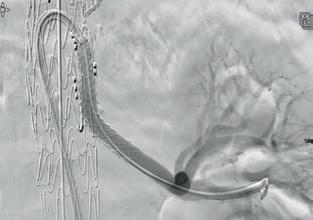

Precise implantation

Exact location and post-expansion